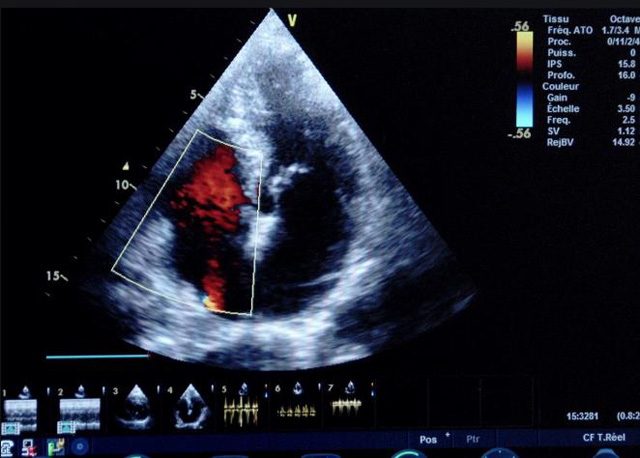

二、彩色室壁運(yùn)動(dòng)分析

(一)基本原理彩色室璧運(yùn)動(dòng)分析,從整體散射數(shù)據(jù)中識(shí)別心內(nèi)膜邊界,并與前一幀彩色不同,心臟收縮或舒張期開(kāi)始到結(jié)束時(shí)心內(nèi)膜的全部過(guò)程。每一次順序顯示結(jié)束后,原來(lái)的彩色自動(dòng)消失,以便進(jìn)入下一個(gè)顯示過(guò)程。其結(jié)果是獲得對(duì)應(yīng)于每一個(gè)心動(dòng)周期的彩色顯示,描繪特定周期內(nèi)室壁運(yùn)動(dòng)的時(shí)間運(yùn)動(dòng)軌跡。

(二)操作步驟根據(jù)背向散射數(shù)據(jù)中將心內(nèi)膜運(yùn)動(dòng)的位移過(guò)程分類為組織或血液的原理,邊緣檢測(cè)跟蹤心內(nèi)膜和血液的界面。橙色表示收縮期的開(kāi)始,收縮期不同時(shí)相逐幀顯示色彩均疊加在收縮末期最后一幀圖像中。檢查時(shí),可按以下步驟進(jìn)行:

①顯示較為理想的二維圖像,常用切面有心尖四腔心、二腔心、左心室長(zhǎng)軸和左心室乳頭肌水平短軸切面。

②啟動(dòng)AQ系統(tǒng),啟動(dòng)后適當(dāng)?shù)卣{(diào)節(jié)增益補(bǔ)償,顯示心內(nèi)膜。

③啟動(dòng)CK系統(tǒng),啟動(dòng)后劃定感興趣區(qū)域。同時(shí)記錄的心動(dòng)圖R波頂點(diǎn)為舒張末期,T波終點(diǎn)為收縮末期,顯示RT間期的CK彩階圖,連續(xù)記錄3~ 5個(gè)心動(dòng)周期。

④對(duì)所獲圖像和數(shù)據(jù)進(jìn)行分析和計(jì)算。

(三)檢測(cè)節(jié)段性室壁運(yùn)動(dòng)異常,研究冠心病患者左心室功能和分析局部室壁運(yùn)動(dòng)過(guò)程中。測(cè)量每一節(jié)段室壁的運(yùn)動(dòng)量,運(yùn)動(dòng)正常的節(jié)段彩帶色彩均勻?qū)哟喂庹?。運(yùn)動(dòng)減弱的節(jié)段,厚度薄層次不全。心內(nèi)膜位移幅度和速度均減低。心內(nèi)膜位移幅度和速度甚低或難以測(cè)得。正常的多層彩帶消失,呈現(xiàn)紅色色帶,心內(nèi)膜位移呈負(fù)向,幅度和速度亦減低。急性心肌梗死的患者中可用于識(shí)別存活心肌抑或壞死心肌。多巴酚丁胺負(fù)荷試驗(yàn)存活心肌的心內(nèi)膜位移幅度增高,停藥后即消失,而壞死心肌則無(wú)上述表現(xiàn)。實(shí)時(shí)檢查冠心病的節(jié)段性室壁運(yùn)動(dòng)異常,有時(shí)候通過(guò)發(fā)現(xiàn)局部心肌運(yùn)動(dòng)的時(shí)相異常,對(duì)于心臟傳導(dǎo)障礙的診斷也可能有幫助。